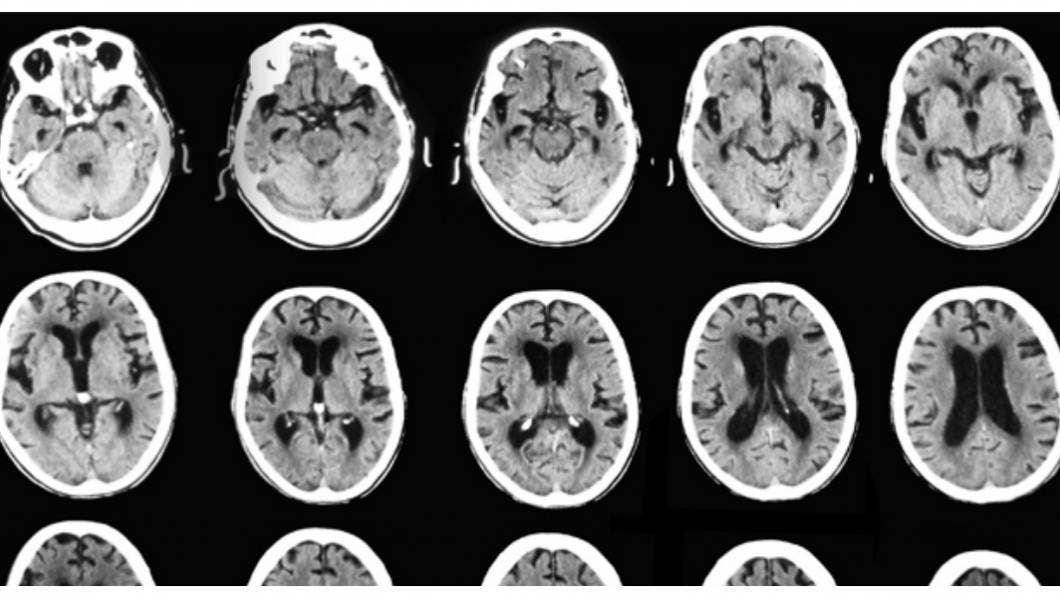

Un nuevo estudio ha descubierto un daño cognitivo en pacientes con COVID-19, en donde los peores casos el declive que han tenido ha sido equivalente a 10 años de deterioro.

Reuters.- La gente que se recupera de Covid-19 podría sufrir impactos significativos en las funciones cerebrales y en el peor de los casos la infección se ha asociado a un deterioro mental equivalente a 10 años de envejecimiento del cerebro, advirtieron el martes investigadores.

Un estudio a más de 84,000 personas, que no ha sido revisado por pares y fue liderado por Adam Hampshire, médico del Imperial College de Londres, halló que en algunos casos graves, la infección de coronavirus está asociada con déficits cognitivos sustanciales durante meses.

Los déficits cognitivos fueron “de una magnitud de efecto sustancial”, especialmente entre las personas que habían sido hospitalizadas con Covid-19, dijeron los investigadores. Los peores casos mostraron impactos “equivalentes al declive promedio de 10 años en el desempeño global entre las edades de 20 a 70”.